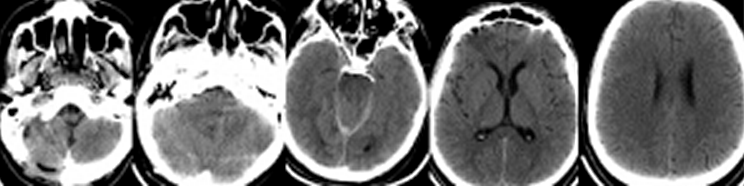

Пациент Н, 28 лет, был переведен в Институт из стационара первичной госпитализации на четвертые сутки после травмы с диагнозом: Ушиб головного мозга: лобных долей, правого полушария мозжечка, травматическое субарахноидальное кровоизлияние. Из анамнеза было известно, что пациент был избит. После кратковременного эпизода утраты сознания был период стабилизации состояния. Госпитализирован в больницу пациент был только через 6 часов после травмы, когда развилось угнетение сознания до сопора и появились мозжечковые нарушения. Тяжесть состояния продолжала нарастать, развился тетрапарез. Пациент был интубирован, началась ИВЛ. При КТ-исследовании головного мозга (по данным выписки из первичного стационара) была выявлена эпидуральная и субдуральная гематома задней черепной ямки (ЗЧЯ). Было произведено удаление гематомы с декомпрессивной трепанацией ЗЧЯ и пластикой твердой мозговой оболочки, установлен наружный вентрикулярный дренаж, который в связи с его дисфункцией позднее, перед переводом в Институт, был удален. После операции состояние оставалось тяжелым, сохранялся сопор и тетрапарез до 0-1 баллов. Была выполнена трахеостомия. На 3 сутки пациент был переведен в Институт Нейрохирургии. Уровень сознания при поступлении оценивался как сопор. Выявлялся тетрасиндром: нижняя параплегия, глубокая верхняя параплегия с возможностью ограниченного приподнимания плеч. Продолжалась ИВЛ. Появилась высокая лихорадка – 38 – 39° С. При КТ-исследовании головного мозга определялись зоны геморрагического пропитывания в базальных отделах правой гемисферы мозжечка, небольшое скопление крови субтенториально с двух сторон и в дорзальных отделах межполушарной щели, контузионные очаги в лобных долях. III желудочек был умеренно расширен. Определялся продольный линейный перелом затылочной кости протяженностью 2,5 см парамедианно справа, в 1,5 см от большого затылочного отверстия (Рисунок 4).

Был вновь установлен наружный вентрикулярный дренаж Codman с возможностью мониторинга ВЧД. При исследовании ликвора был диагностирован менингит – цитоз ликвора - 4320/3, нейтрофильный, глюкоза ликвора составила 30% от уровня глюкозы в плазме, лактат ликвора был повышен до 3,8 ммоль/л., Внутричерепной гипертензии не отмечалось. Была назначена антибактериальная терапия Меропенемом и Ванкомицином. Продолжалась ИВЛ. Несмотря на коррекцию антибактериальной терапии в течение следующих суток лихорадка стала более выраженной, достигая 40-40,5° С, резистентная к парацетамолу, НПВС и наркотическим анальгетикам. На этом фоне развилось угнетение сознание до поверхностной комы, исчезли движения плеч. Была начата ИН по вышеприведенному протоколу. Через 5 часов была достигнута нормотермия – 36,9 – 37,3° С в мочевом пузыре. Вместе с этим постепенно, в течение следующих суток у пациента повысился уровень бодрствования и спонтанной активности, вновь появились движения в плечах. ИН продолжалась в течение 5 суток. На фоне антибактериальной терапии была достигнута нормализация ликвора в течение недели, вентрикулярный дренаж был удален на 12 сутки. К этому времени уровень сознания возрос до сомноленции, восстановились движения в руках, начался регресс нижней параплегии. ИВЛ продолжалась в течение 18 суток. На 23 сутки пациент был переведен в нейрохирургическое отделение. На 25 сутки в связи с восстановлением адекватного глотания произведена декануляция. Пациент был выписан из Института на 56 сутки, по ШИГ его состояние оценивалось в 4 балла.